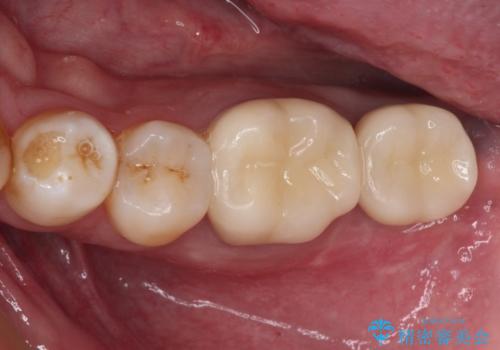

インプラントにはストローマン社のSLActiveを使用し、埋入から補綴までおよそ3か月と、短期間で治療を進めることができました。